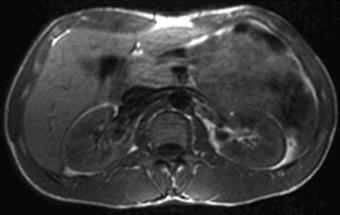

| Рис. 6.6. МРТ брюшной полости на уровне L2. Аксиальное Т1-ВИ нормальных почек. |